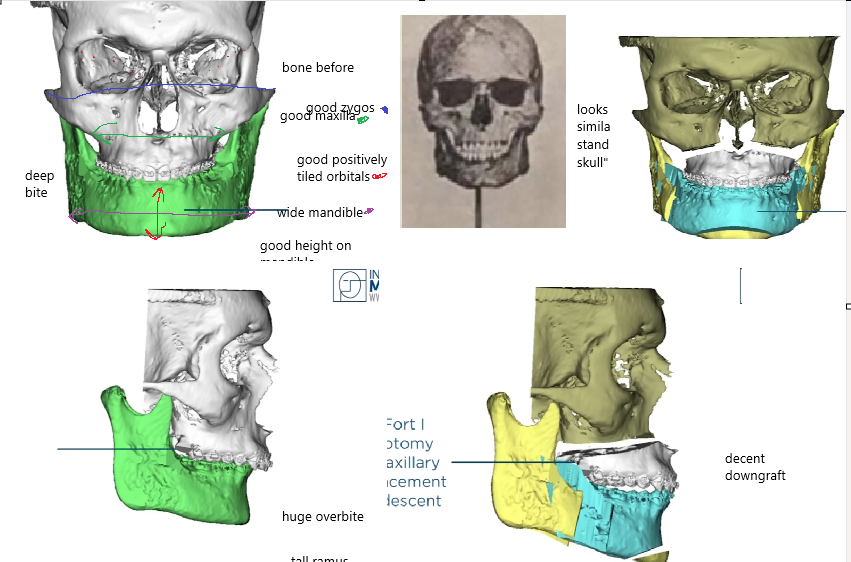

Lets start with gustavo, Alfaro bimax case, the most famous bimax result online:

lets look at his skeleton, which explains the huge transformation:

Lets start with gustavo, Alfaro bimax case, the most famous bimax result online:

lets look at his skeleton, which explains the huge transformation: